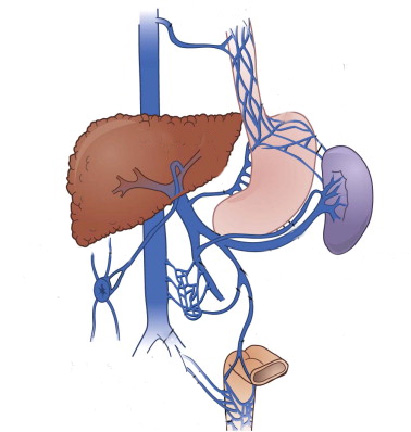

O que é um exame de CPRE (colangiopancreatografia retrógrada endoscópica)?

A CPRE é um procedimento que pode ser feito para examinar o fígado, vesícula biliar, vias biliares e o pâncreas. O fígado é um órgão que, entre outras coisas, produz um líquido chamado bile que auxilia a digestão. A vesícula biliar é um órgão pequeno, em forma de pêra, que armazena a bile até que seja necessária para a digestão. Os ductos biliares são canais que transportam a bile do fígado para a vesícula biliar e duodeno. Estes ductos são chamados algumas vezes de árvore ou via biliar. O pâncreas é um órgão que produz substâncias químicas que ajudam a digestão.

Com o paciente sedado, o aparelho é introduzido pela boca e passa através do esôfago e do estômago para o duodeno, local onde fica posicionada a papila duodenal.

Para o exame, o médico utiliza um tubo flexível e iluminado chamado duodenoscópio, que possui uma câmera na lateral do aparelho, diferente do endoscópico padrão que possui a câmera na frente do aparelho.

O médico verifica a abertura do tubo de drenagem de bile do fígado. Este tubo de drenagem é chamado de ducto biliar comum. Drena bile do fígado e suco pancreático para o duodeno para ajudar na digestão das gorduras. O orifício de saída do ducto biliar no parede do duodeno chama-se papila duodenal.

Durante o exame o médico passa de um pequeno cateter (tubo) dentro do ducto biliar comum e injeta um contraste que pode ser visto com um exame de raio-X. A via biliar e eventualmente o pâncreas podem então ser examinados para anormalidades.

A CPRE pode ser utilizada para o tratamento de pedras ou bloqueios nos canais biliares. Seu médico pode usar alguns acessórios para fazer um pequeno corte na parede do intestino, na abertura do duto biliar comum para alargar a abertura da papila duodenal. Este procedimento chama-se papilotomia endoscópica.

Após este procedimento, pode ser possível a retirada de cálculos da via biliar, permitindo assim o retorno normal da drenagem da bile do fígado para o duodeno.

Pode-se também realizar a passem de prótese através da abertura, para drenar a via biliar em caso de grande cálculos ou tumores que possam estar obstruindo a região.

O que é um exame de CPRE (colangiopancreatografia retrógrada endoscópica)?

A CPRE é um procedimento que pode ser feito para examinar o fígado, vesícula biliar, vias biliares e o pâncreas. O fígado é um órgão que, entre outras coisas, produz um líquido chamado bile que auxilia a digestão. A vesícula biliar é um órgão pequeno, em forma de pêra, que armazena a bile até que seja necessária para a digestão. Os ductos biliares são canais que transportam a bile do fígado para a vesícula biliar e duodeno. Estes ductos são chamados algumas vezes de árvore ou via biliar. O pâncreas é um órgão que produz substâncias químicas que ajudam a digestão.

Com o paciente sedado, o aparelho é introduzido pela boca e passa através do esôfago e do estômago para o duodeno, local onde fica posicionada a papila duodenal.

Para o exame, o médico utiliza um tubo flexível e iluminado chamado duodenoscópio, que possui uma câmera na lateral do aparelho, diferente do endoscópico padrão que possui a câmera na frente do aparelho.

O médico verifica a abertura do tubo de drenagem de bile do fígado. Este tubo de drenagem é chamado de ducto biliar comum. Drena bile do fígado e suco pancreático para o duodeno para ajudar na digestão das gorduras. O orifício de saída do ducto biliar no parede do duodeno chama-se papila duodenal.

Durante o exame o médico passa de um pequeno cateter (tubo) dentro do ducto biliar comum e injeta um contraste que pode ser visto com um exame de raio-X. A via biliar e eventualmente o pâncreas podem então ser examinados para anormalidades.

A CPRE pode ser utilizada para o tratamento de pedras ou bloqueios nos canais biliares. Seu médico pode usar alguns acessórios para fazer um pequeno corte na parede do intestino, na abertura do duto biliar comum para alargar a abertura da papila duodenal. Este procedimento chama-se papilotomia endoscópica.

Após este procedimento, pode ser possível a retirada de cálculos da via biliar, permitindo assim o retorno normal da drenagem da bile do fígado para o duodeno.

Pode-se também realizar a passem de prótese através da abertura, para drenar a via biliar em caso de grande cálculos ou tumores que possam estar obstruindo a região.